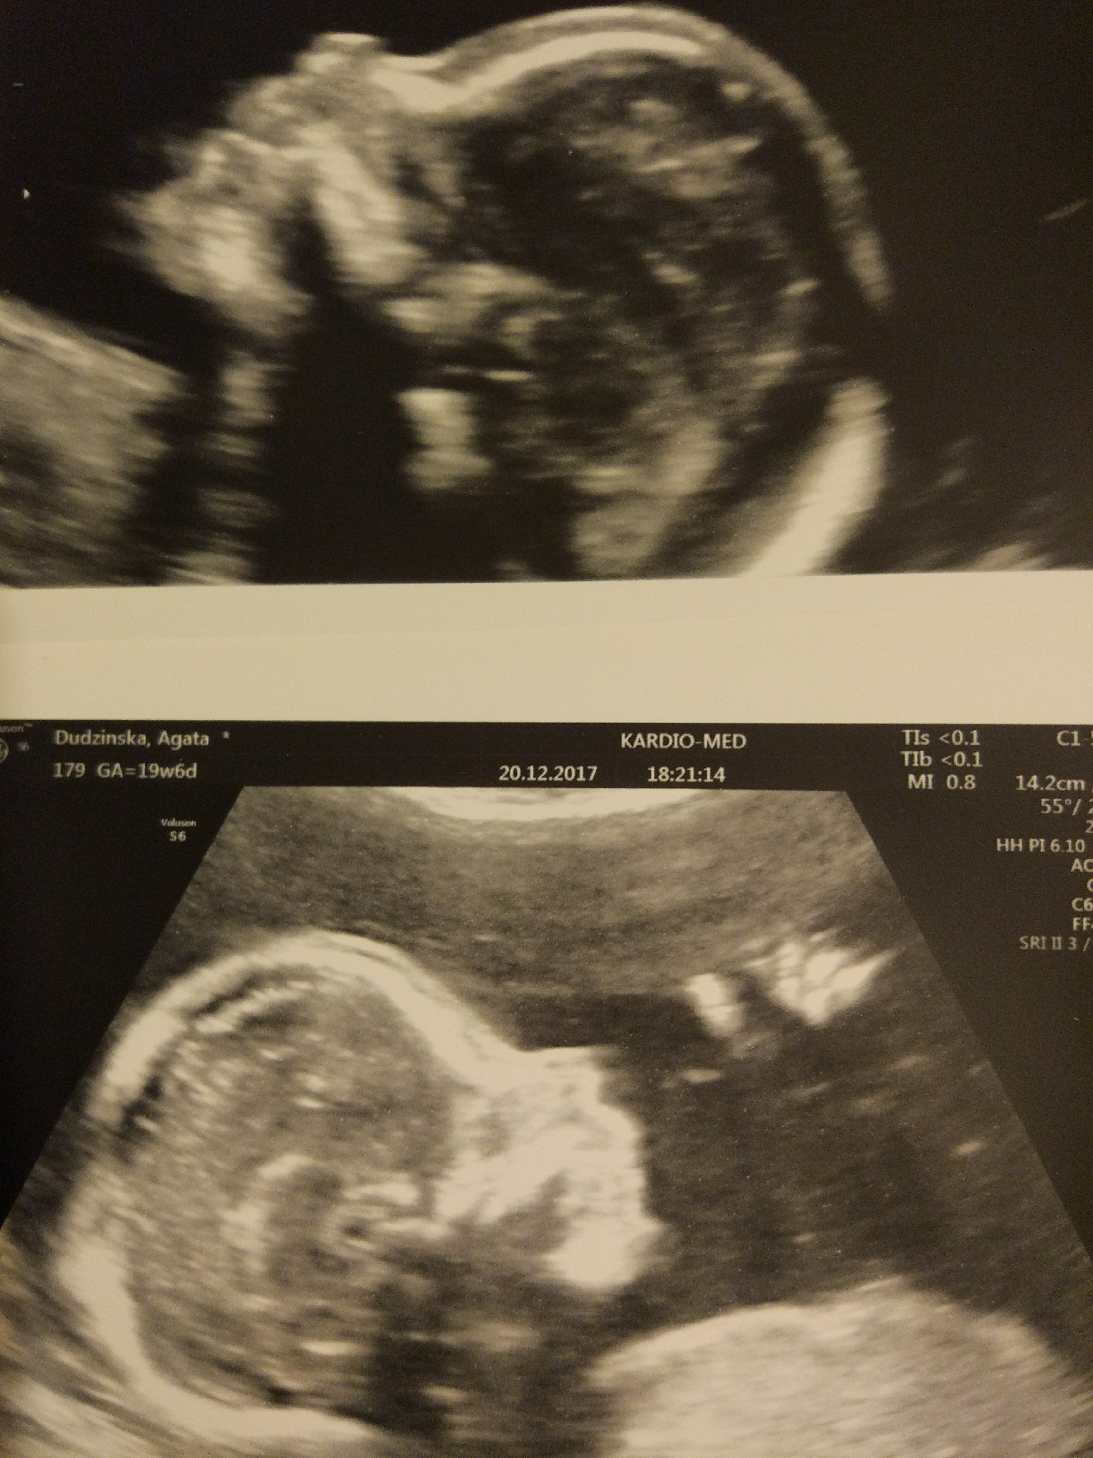

Ja dziś też po połówkowych. Wszystko dobrze, 350g. Strasznie ciężki do zbadania przez ruchliwość. I jest duża różnica w szczegółowości badania między zwykłym połówkowym a szukaniem ewentualnych wad- ten sam lekarz a inaczej wyglądała wizyta dziś niż u córki